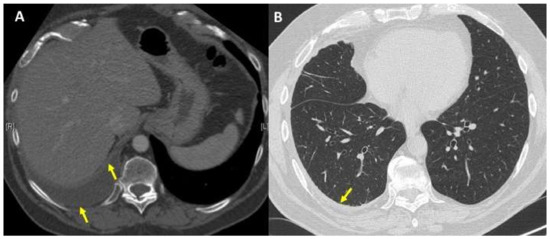

2. Case Presentation